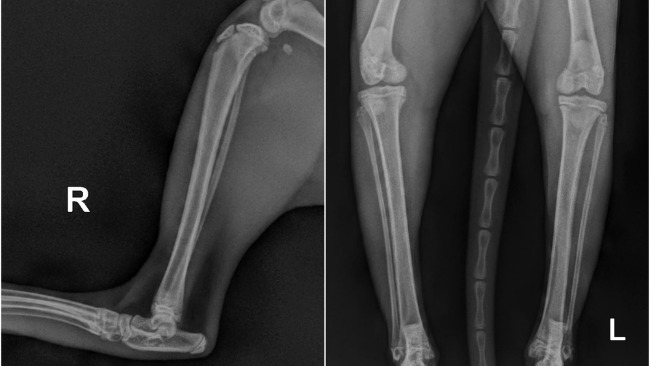

Gdy jesteś młodym kotkiem, takim jak nasza Panda, chcesz biegać, skakać, wspinać się po drapaku na sam szczyt. Niestabilne rzepki w kolanach uniemożliwiają koteczce normalne funkcjonowanie :( Po konsultacji u ortopedy, Panda ma wskazanie na pilne zabiegi rekonstrukcji rzepek - pierwsza już w najbliższą środę.